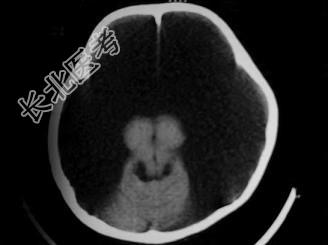

- 单项选择题女,1岁半, 头颅迅速增大,行CT检查如图, 请选出最可能的诊断  (    )

A、积水型无脑畸形

B、硬膜外血肿

C、硬膜下血肿

D、硬膜下积液

E、脑内血肿